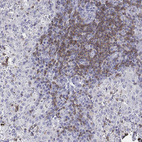

Immunohistochemistry analysis in human lymph node and small intestine tissues using HPA040957 antibody. Corresponding CD3E RNA-seq data are presented for the same tissues.